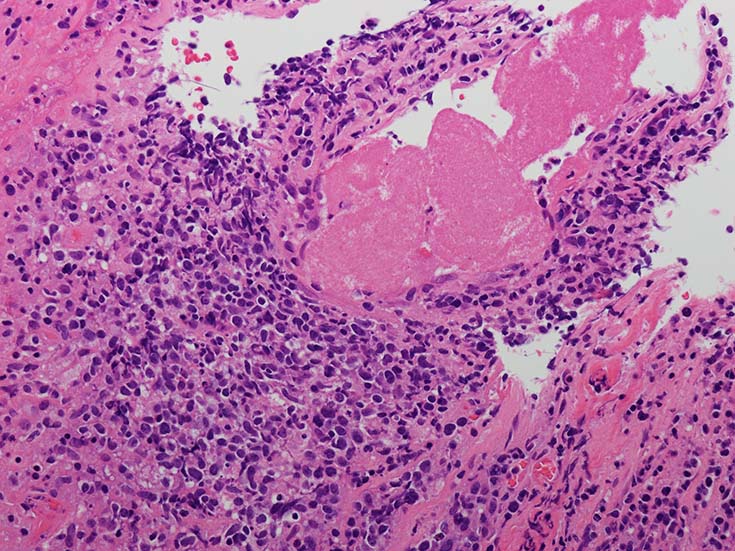

血管周囲性に大型類円形核や不整形核をもつ腫瘍細胞がシート状密に浸潤増殖している. Mitosisが多く認められる.細血管閉塞や破壊の所見がある.

間質にもシート状の腫瘍細胞浸潤がある. 大小 pleomorphicな傾向.(A, B). necrosisが認められる(C). 細気管支上皮直下まで密な浸潤あり, 小型リンパ球が混在している.(D)

血管中心性浸潤. 障害された血管内に血栓が形成されている.CD20陽性細胞がシート状密に浸潤, CD3陽性T細胞が多く混在している. EBER-ISH陽性 EBV感染細胞が多数認められ, >50 hpf, 定義より Grade3となる. 陽性細胞のサイズは大小さまざまであることに注意.